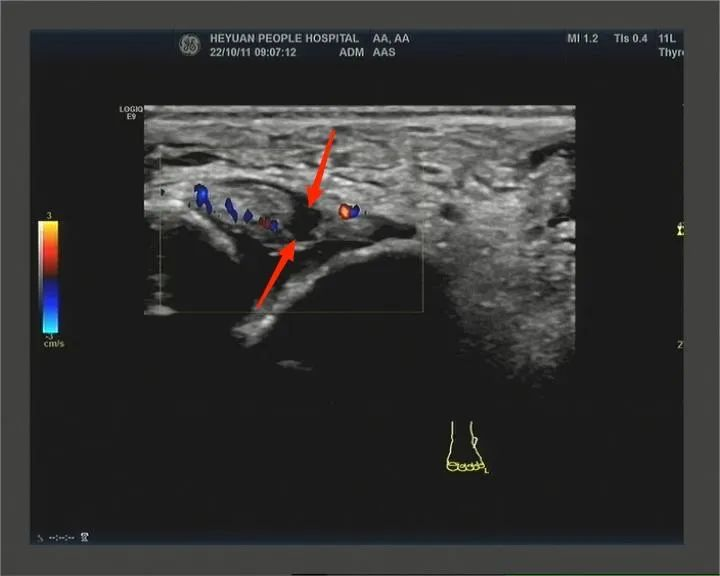

检查是否存在肌肉、肌腱、韧带等软组织的急慢性损伤。常见的急性损伤类型包括肩袖损伤、跟腱断裂、韧带撕裂、肌肉血肿等;常见的慢性损伤类型包括腱鞘炎、筋膜炎等。

距腓前韧带完全性撕裂伤